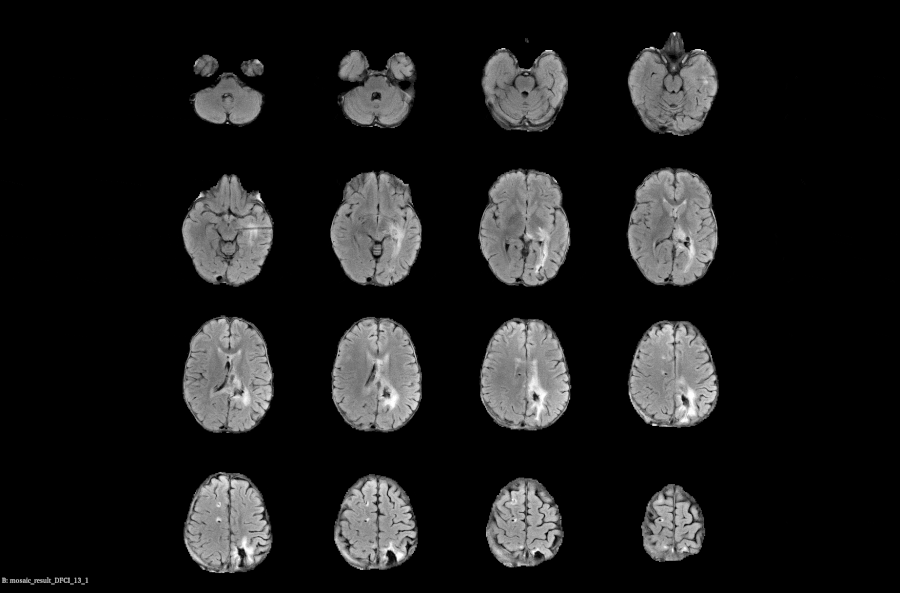

Voiant Hub 2.0 streamlines segmentation and tracking for semi-automated RECIST and volumetric automated RANO assessments, enhancing accuracy, consistency, and compliance in tumor response and tumor burden evaluation.

- RANO; mRANO, RANObm; RANO 2.0

Powered by Voiant Hub 2.0, our platform captures early biological signals and enables advanced, volumetric tumor characterization—unlocking a growing portfolio of imaging biomarkers that refine trial eligibility, accelerate exploratory endpoints, and drive targeted, image-informed strategies:

Additional MRI

- ADC

- Blood Volume

- Perfusion and Permeability

- T2 & Fat Water Mapping